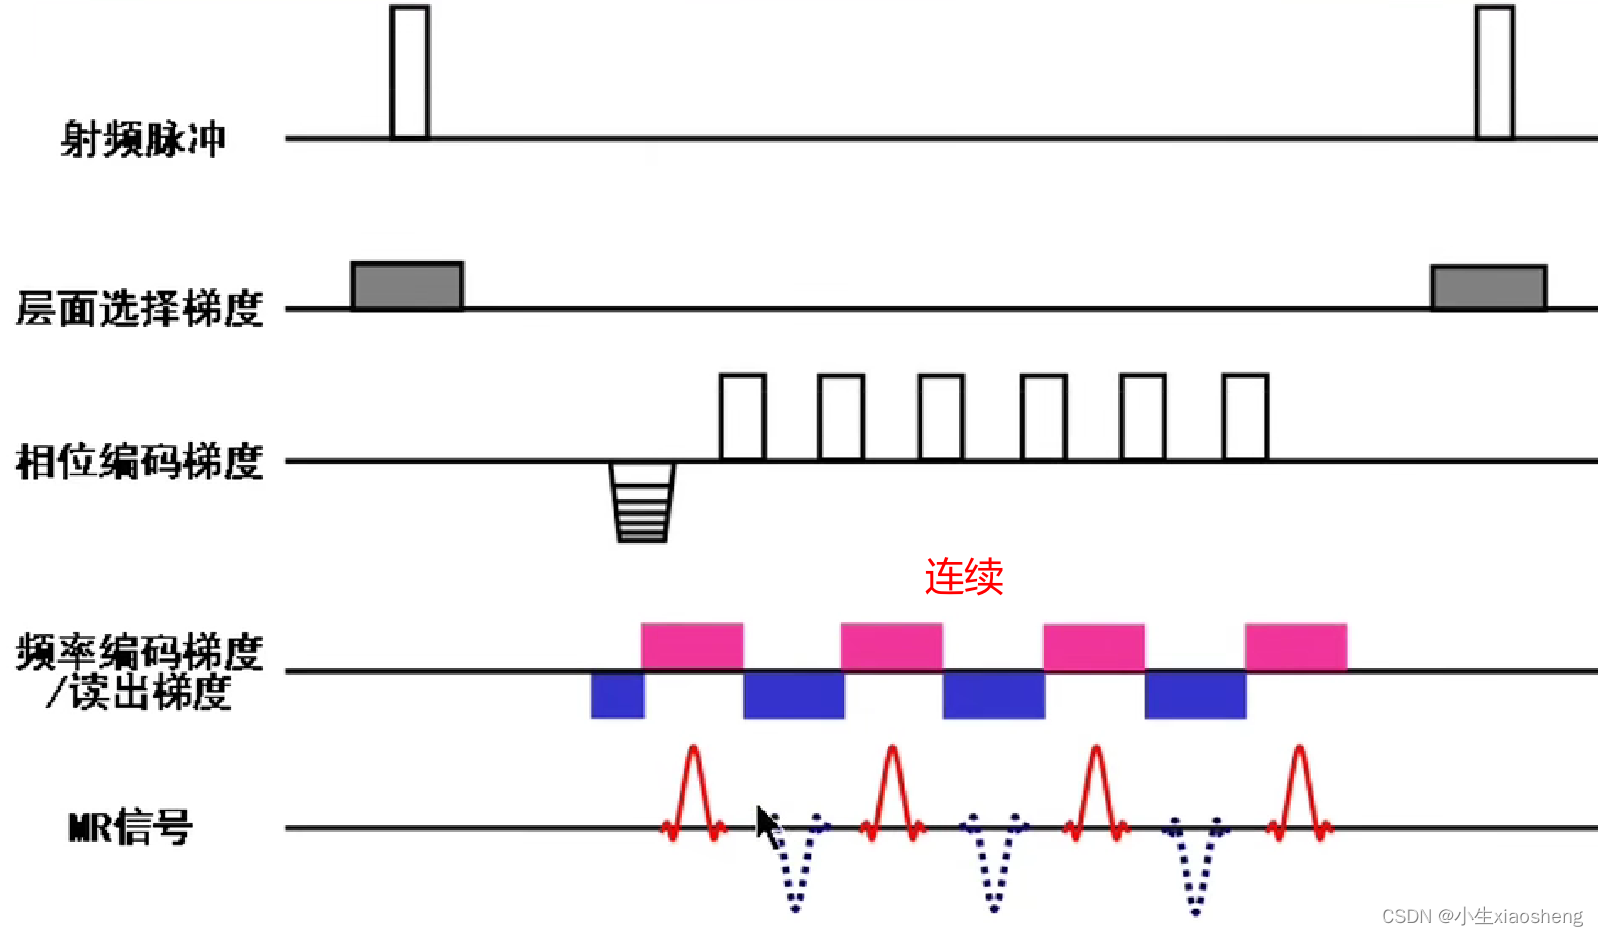

七、EPI序列

当然连续时不会像单次激发那样把整个K空间填满,还是需要经过几个90度脉冲。

自旋回波--90度和180度填充K空间;反转恢复--在自旋的基础上两边加180度;梯度回波--消除每次脉冲留下的影响,以及波的次数;propeller==》K空间填充技术和FSE或FIR结合用于减少运行伪影;EPI==》采集方式,一次激发采集多个回波的形式但与单次不一样;PRESTO和GRASE==》前面几种的一种结合形成新的。